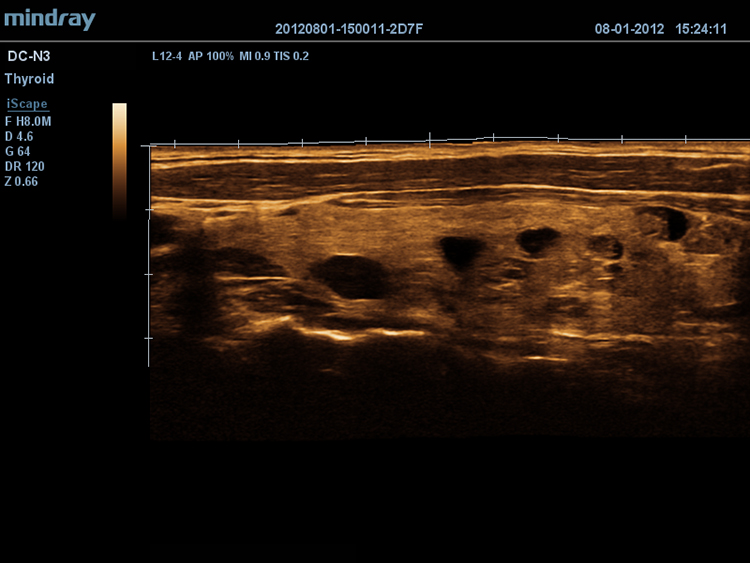

iScapeTM

–Ф–∞–µ—В –њ–Њ–ї–љ—Л–є –Є —А–∞—Б—И–Є—А–µ–љ–љ—Л–є –Њ–±–Ј–Њ—А –∞–љ–∞—В–Њ–Љ–Є—З–µ—Б–Ї–Є—Е —Б—В—А—Г–Ї—В—Г—А –њ–Њ—Б—А–µ–і—Б—В–≤–Њ–Љ –њ–∞–љ–Њ—А–∞–Љ–љ–Њ–є –≤–Є–Ј—Г–∞–ї–Є–Ј–∞—Ж–Є–Є, –≤ —Б–Њ—З–µ—В–∞–љ–Є–Є —Б –Є–љ–і–Є–Ї–∞—В–Њ—А–Њ–Љ —Б–Ї–Њ—А–Њ—Б—В–Є –Є —Д—Г–љ–Ї—Ж–Є–µ–є –њ—А—П–Љ–Њ–≥–Њ / –Њ–±—А–∞—В–љ–Њ–≥–Њ —Б–Ї–∞–љ–Є—А–Њ–≤–∞–љ–Є—П, –і–µ–ї–∞—П –њ—А–Њ—Ж–µ—Б—Б –±–Њ–ї–µ–µ –ї–µ–≥–Ї–Є–Љ, –њ–Њ—Б–ї–µ–і–Њ–≤–∞—В–µ–ї—М–љ—Л–Љ –Є —Г–њ—А–∞–≤–ї—П–µ–Љ—Л–Љ.